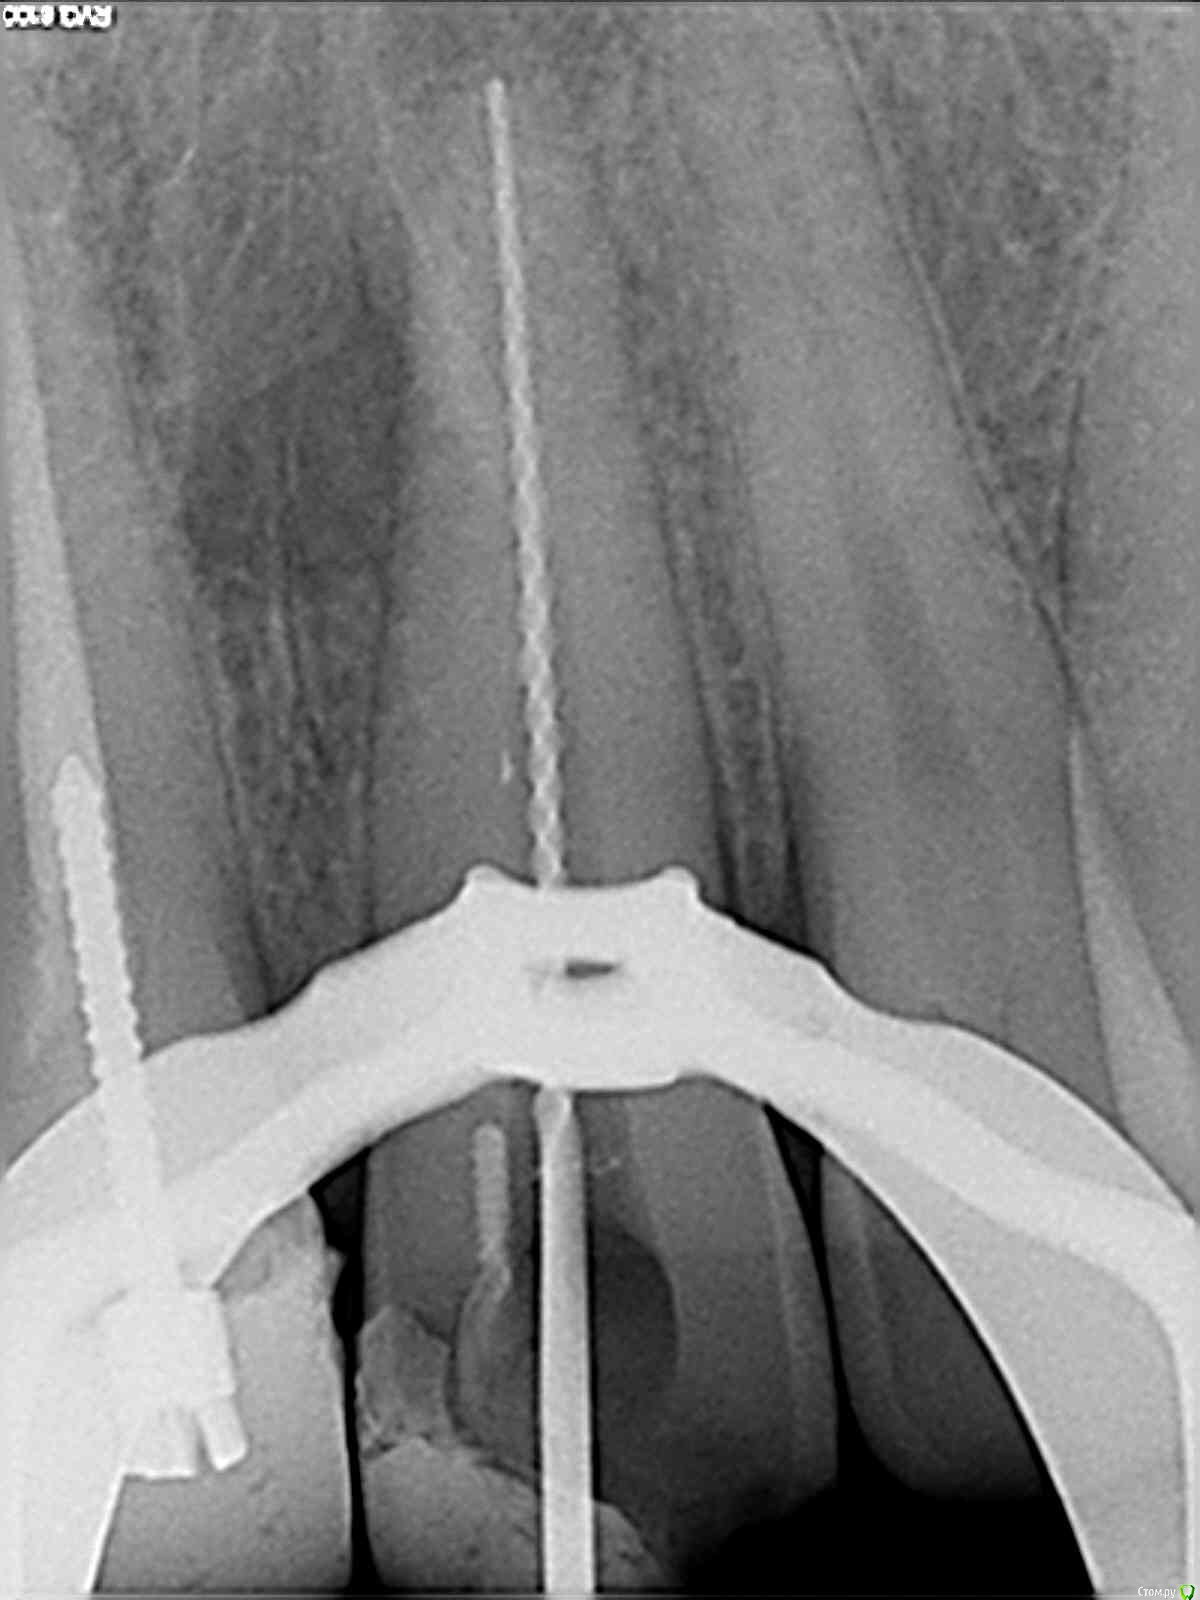

DmitrySH Опубликовано 5 февраля, 2019 Поделиться Опубликовано 5 февраля, 2019 3д режим не надо, сделайте срезы по оси центральных резцов Ссылка на комментарий

vlazub Опубликовано 5 февраля, 2019 Автор Поделиться Опубликовано 5 февраля, 2019 [/url][/url] Ссылка на комментарий

vlazub Опубликовано 5 февраля, 2019 Автор Поделиться Опубликовано 5 февраля, 2019 [/url] Ссылка на комментарий

vlazub Опубликовано 5 февраля, 2019 Автор Поделиться Опубликовано 5 февраля, 2019 11 зуб[/url] Ссылка на комментарий